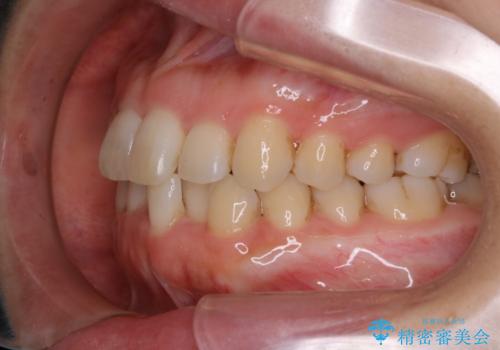

インビザライン・ライトでの抜歯矯正治療 (スリーインサイザー仕上げ)

- 上下の前歯のがたつきが気になるとのことで来院されました。最短治療とインビザラインでの矯正治療をご希望されました。

前歯のがたつきを無くすためには、スペースを確保する必要があります。上の前歯のがたつきは軽度ながたつきのため、歯と歯の間を研磨をして、そのスペースを使い並べていきます。下の前歯は、1本前歯を抜いて研磨せずに、その抜歯したスペースを使い並べることになりました。

インビザライン・ライトにて矯正治療を行うことになりました。

下の前歯は、スリーインサイザー仕上げと言って、通常前歯は4本ありますが(犬歯はいれていない)、そのどれか1本を抜歯して前歯を3本にして矯正治療を行うことを言います。また、先天的に歯の本数が少ない方もいますので、矯正治療を行っていなくても元々スリーインサイザーの方もいます。